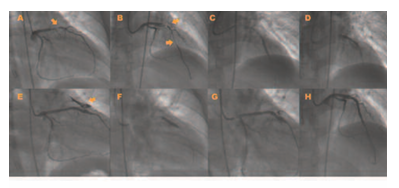

Manejo de la rotura coronaria y sus complicaciones durante la angioplastia en una paciente portadora de lupus eritematoso sistémico